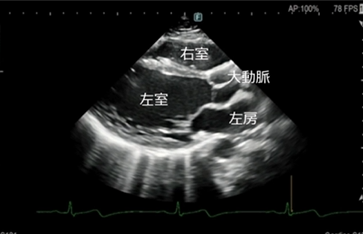

エコー(心臓超音波)検査

- このようなことが分かります

弁膜症の評価

心臓の弁(大動脈弁・僧帽弁など)の開き具合や逆流の有無を確認します。

弁の狭窄や逆流の程度を評価し、治療方針の判断に役立てます。 - 心筋の働き(ポンプ機能)の評価

心臓がどのくらいしっかり血液を送り出せているか(収縮機能)を確認します。

心筋梗塞後の機能低下や、拡張型心筋症などの診断にも重要です。 - 心不全の原因検索

息切れやむくみなどの心不全が疑われる場合、その原因が弁膜症によるものか、心筋の

弱りによるものかを詳しく調べます。 - その他

心肥大の有無・心臓内血栓の確認・先天性心疾患の評価・肺高血圧症の推定 など - 検査について

検査時間はおおよそ20~30分程度です。

ベットに横になっていただき、胸にゼリーを塗ってプローブ(探触子)を当て観察します。痛みはありません。

当院では、循環器疾患の早期発見と適切な治療につなげるため、症状がある方は、もちろん、健診等で指摘された方にも心エコー検査を行っております。

超音波診断装置

当院の超音波診断装置(エコー装置)は、高画質で多彩なプローブバラエティと臨床アプリケーションにより、腹部・表在・循環器などの幅広い分野での検査が行えます。当製品はPrecision Imagingを搭載し、超音波画像を形成する信号を処理することにより、組織信号を強調し、生体内組織の境界などの構造視認性を高め、腫瘍部分などがより描出しやすくなっております。